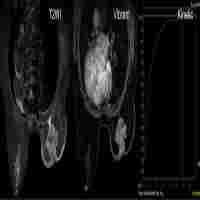

Abbreviated MR Protocols in Prostate MRI

| Description | Prostate MRI is an integral part of the clinical work-up in biopsy-naïve patients with suspected prostate cancer, and its use has been increasing steadily over the last years. To further its general availability and the number of men benefitting from it and to reduce the costs associated with MR, several approaches have been developed to shorten examination times, e.g., by focusing on sequences that provide the most useful information, employing new technological achievements, or improving the workflow in the MR suite. This review highlights these approaches; discusses their implications, advantages, and disadvantages; and serves as a starting point whenever an abbreviated prostate MRI protocol is being considered for implementation in clinical routine. |